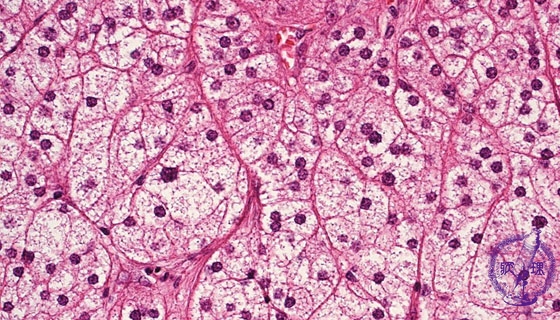

• š(13)Adrenocortical adenoma (Cushing syndrome)

Microscopic findings (HE stain, high power view). Clear cells with lipid-rich foamy cytoplasm. These tumor cells are similar to the cells of zona glomerulosa in adrenal cortex.